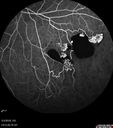

51 year old male with a broken vein in the left eye. His vision is pretty good. He has not noticed any vision change. You asked him to come here for further evaluation in the left eye. VA OD: sc20/63 PH20/25-2 NccJ1 VA OS: sc20/20 Patient had scatter laser to non-perfused retina and never had a vitreous hemorrhage (yet)

Coats' Disease -51 year old asymptomatic male450 views20/20 vision - had laser to non-perfusion because of proliferation.00000